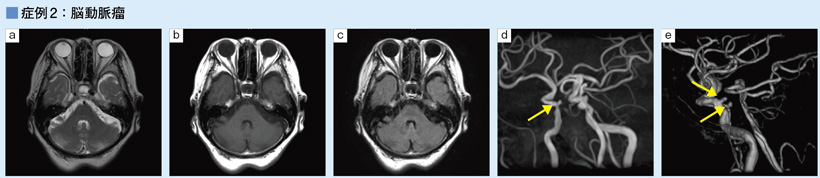

3D MRA画像で,複数の動脈瘤が確認できる(d,e →)。通常の T2強調画像(a),T1強調画像(b),FLAIR(c)でも動脈瘤が確認できる。

a:T2WI,TR/TE:4000/96,スライス厚:5.0mm,RAPID:1.5併用,撮像時間1分21秒

b:T1WI,TR/TE:400/11.3,スライス厚:5.0mm,RAPID:1.6併用,撮像時間1分54秒

c:FLAIR,TR/TE/TI:9000/108/2300,スライス厚:5.0mm,RAPID:1.6併用,撮像時間1分49秒

d:3D MRA,TR/TE:23.0/6.9,FA:20,スライス厚:1.2mm,RAPID:1.6併用,撮像時間4分03秒

e:dのVR像